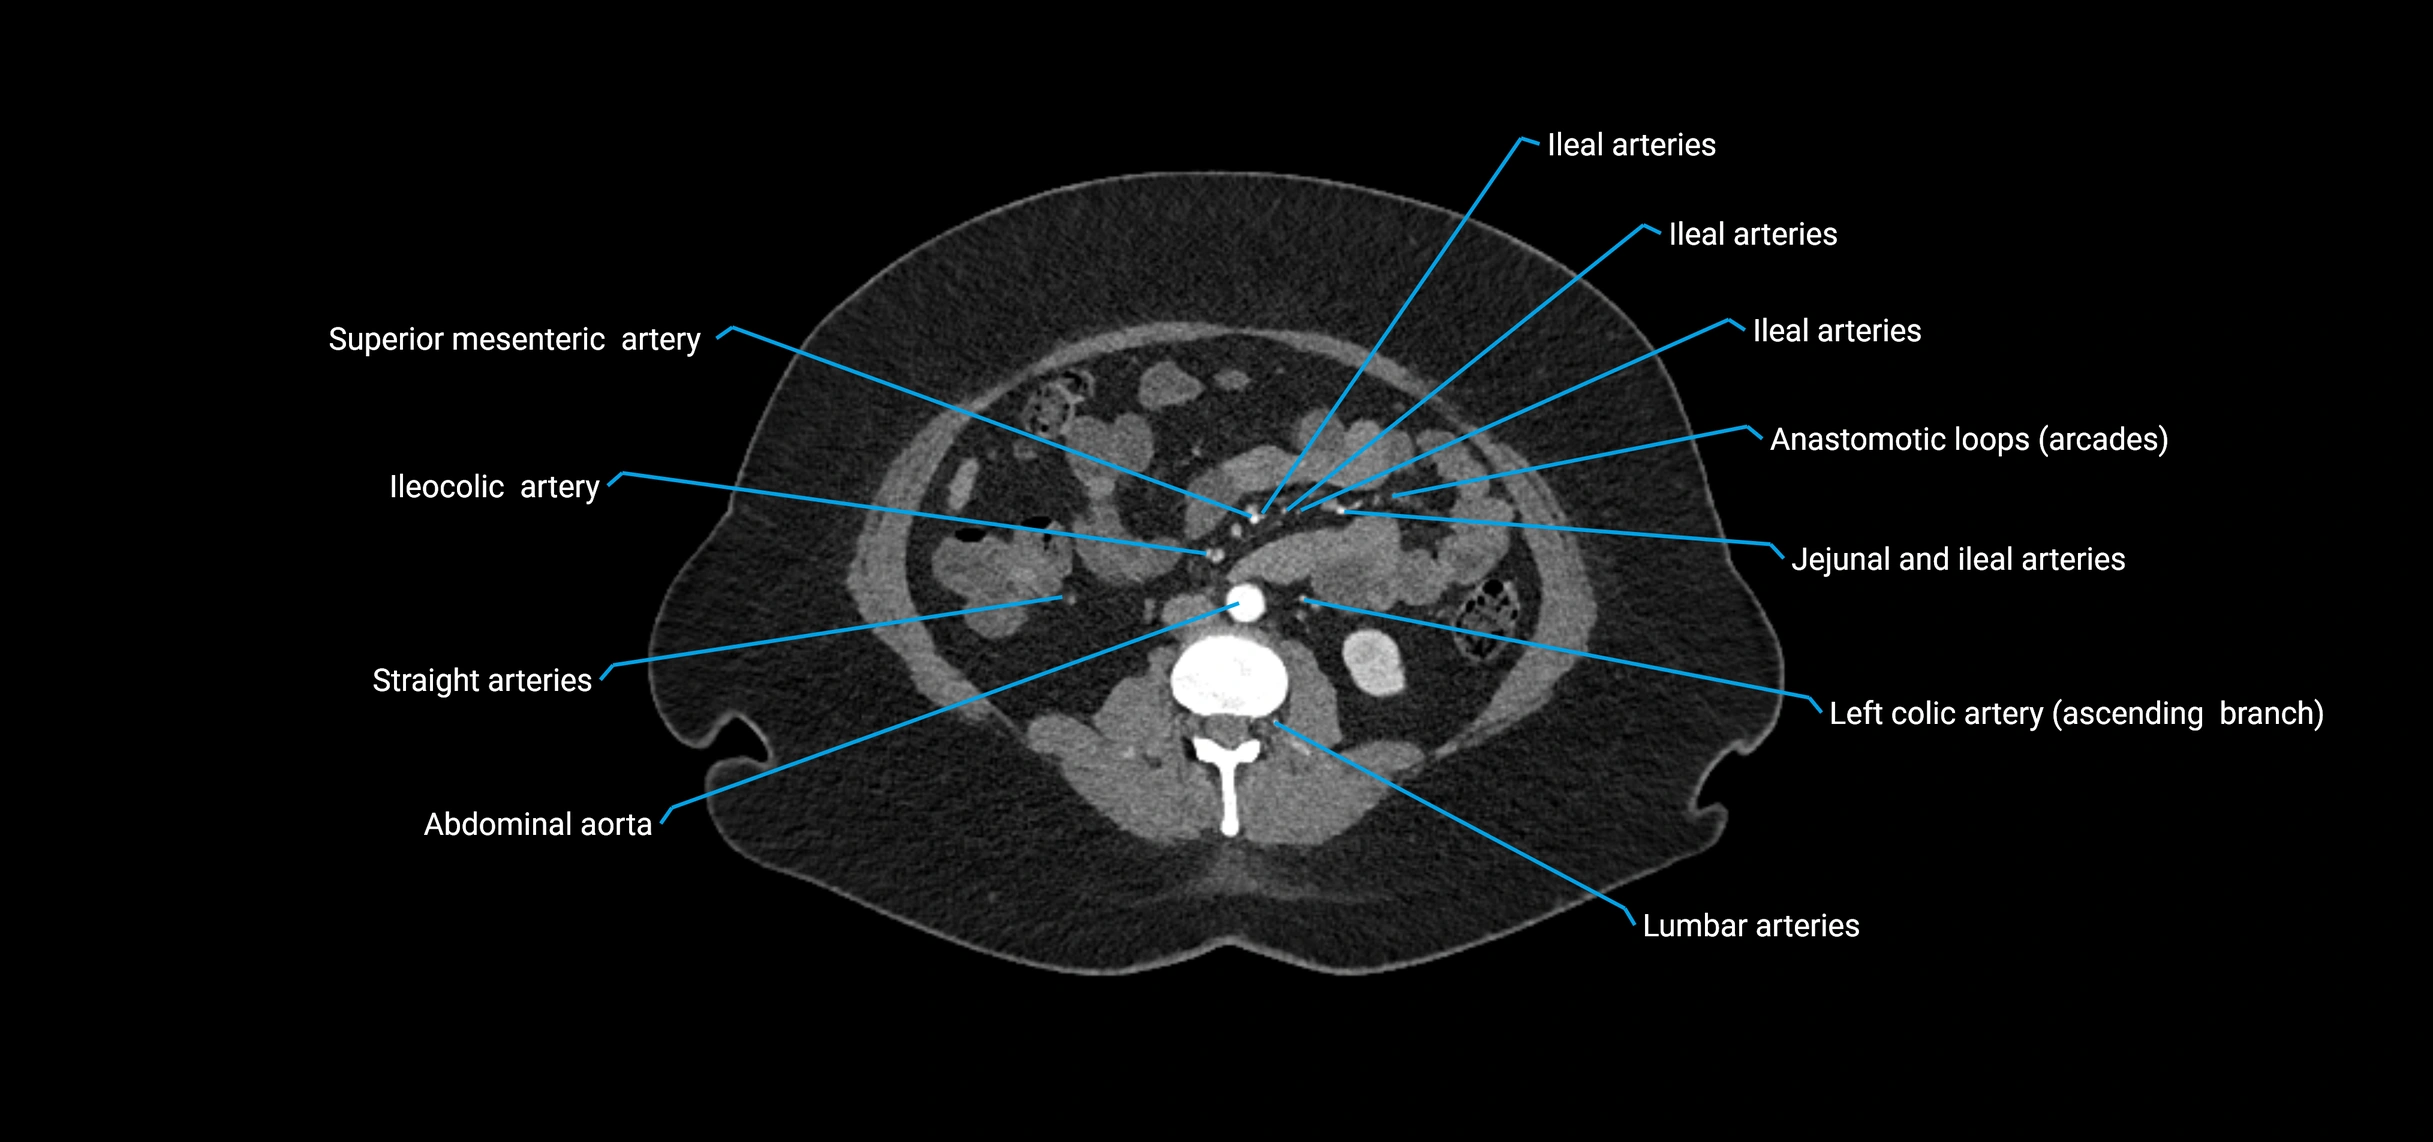

Contrast-enhanced CT (CTA):

• Gold standard for abdominal aortic imaging

• Provides excellent detail of lumen, wall, aneurysm, thrombus, and branch vessels

• Multiplanar and 3D reconstructions help in aneurysm measurement, stent graft planning, and dissection evaluation